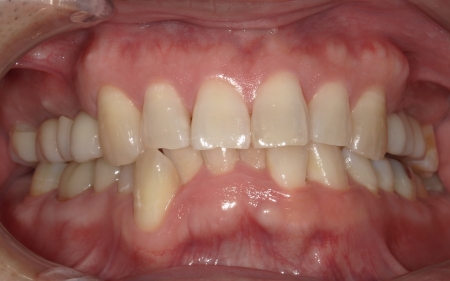

患者様は「可能な限り自分の歯を残したい」と希望されており、長期的な安定と清掃のしやすさを考慮して、②のインプラントブリッジによる治療を選択されました。

抜歯後は骨や歯茎の回復を待ち、口腔内の状態が安定した段階で、インプラント埋入手術へ進みました。

インプラントは、右上4番目と6番目の位置、左上4番目と6番目の位置に埋め込みます。

インプラントがしっかりと骨に定着したことを確認したら、精密な型取りを行い、ブリッジを作製して装着しました。

インプラント治療と併せて保存可能な歯の治療も進め、右上の一番奥の歯と右下の奥歯(前から5番目と6番目)に対して、細菌感染した神経を取り除いてから薬を詰める根管治療を行い、CAD/CAM冠という白い被せ物で修復しました。

さらに、上前歯(右上の犬歯から左上の犬歯まで)、右下の4番目の歯に対しては、虫歯治療を行っています。

最後に、痛みや違和感がないか、見た目や噛み合わせに問題がないかを確認し、治療を終了しました。